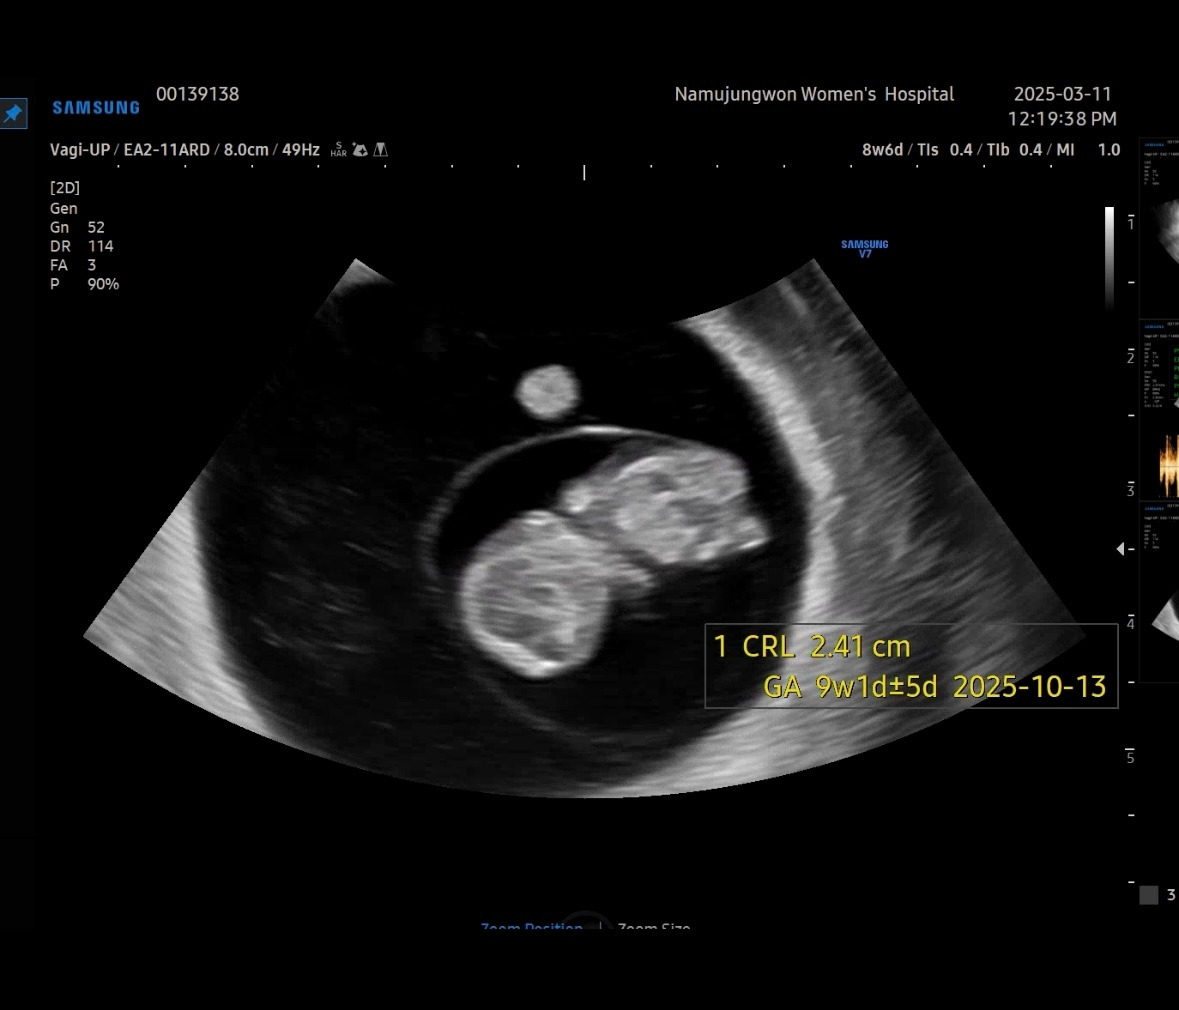

8주 차 6일. 아기가 하리보 젤리를 닮았다고 해서 젤리곰 시기라고 많이 부른다. 의사 선생님이 하리곰 모양을 예쁘게 잡아서 머리, 팔, 다리, 심장을 알려주셨다.

이제야 2.41cm가 된 유민이 젤리곰. 너무 귀엽다.

아니 젤리곰이 이제는 정말 사람 같네! 콧대가 제법 올라와 옆모습인 걸 알아보겠다. 이제는 좌뇌, 우뇌, 신장, 간 위치도 잡아주셔서 정말 신기했다.

이 날은 병원에서 1차 무료로 3D 초음파 영상을 보여주었다.

팔다리가 더 또렷이 보이고 배에 연결되어 있는 탯줄도 보인다. 기지개도 켜고 잘 움직이는 유민이.